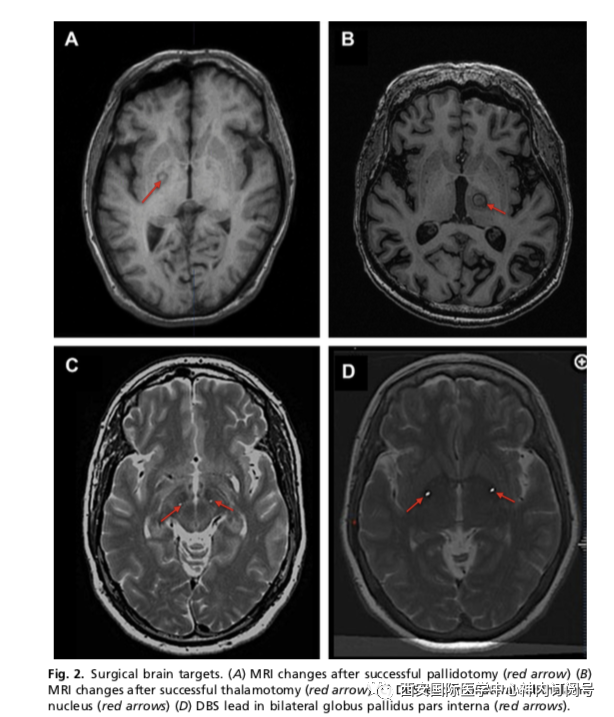

MRI引导的聚焦超声检查(FUS)是一种新的方法,已显示出治疗运动障碍的希望。 将患者放置在带有已安装的MRI兼容超声换能器的立体定向头架中。然后通过MRI直接瞄准,超声能量逐渐增加到目标的消融温度。 外科医生通过患者醒着的术中临床震颤评估来评估病变的疗效,并在高温永久性损伤之前通过MRI测温仪评估病变的大小和位置。在特发性震颤中是阳性的结果,PD的探索性研究正在进行中。 在小型研究中,单侧FUS丘脑切开术在震颤为主的PD患者中被证明是安全有效的,可减少震颤和改善生活质量,而没有观察到对情绪或认知的损害。 初步研究探讨FUS苍白球切开术对PD相关运动障碍并发症的患者疗效,显示其可以改善药物关期的运动评分,随访1年时持续减轻运动障碍(图2)。

图2.手术靶点    (A)苍白球切开术成功后MRI改变(红色箭头)(B)丘脑切开术成功后MRI改变(红色箭头)(C)双侧丘脑底核的DBS导线部位(红色箭头)(D)双侧苍白球内部的DBS导线部位(红色)箭头)。

PD患者理想的DBS靶点(STNGPi)选择仍存在争议(见图2)。 一些研究表明,与GPi相比,STN刺激的药物关期运动残疾和运动迟缓的次要结果有更大的改善,而包括上述研究在内的许多研究表明,不同靶点的整体运动结局没有差异。鉴于缺乏强有力的证据表明靶点之间存在显着的运动差异,可能的认知和情绪副作用经常被考虑,